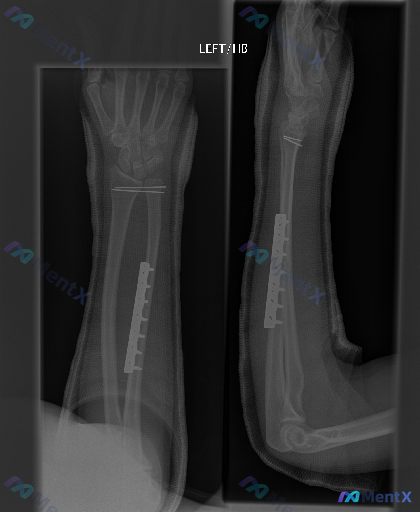

各位同道,今天我们来讨论一份左前臂术后的X线片。患者为左前臂骨折术后复查,拍摄了左前臂正位(AP)和侧位(Lateral)X光片。影像可见左前臂尺骨骨干中段金属钢板及多枚螺钉内固定影,桡骨远端两枚克氏针横穿固定影,肢体周围有高密度石膏/夹板外固定影。尺、桡骨解剖位置大致正常,腕关节间隙可见,关节面轮...